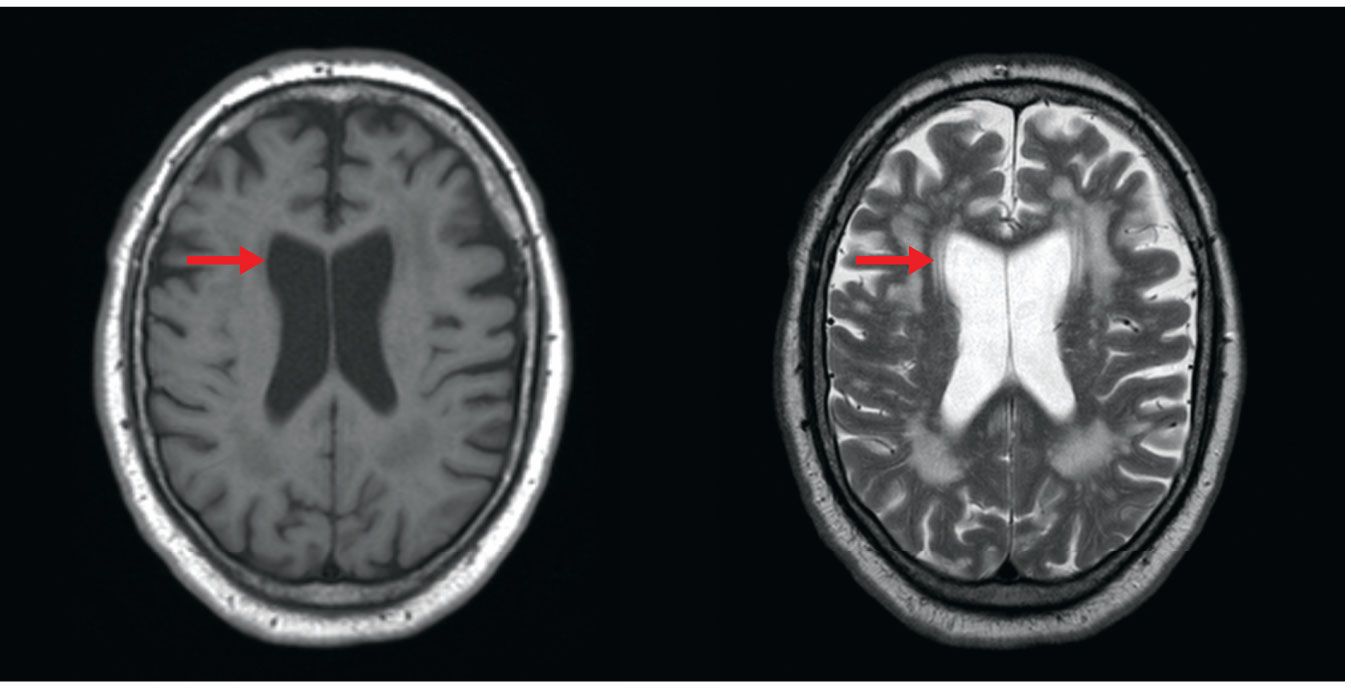

Qualitative evaluation of weighted images by a trained radiologist is an effective diagnostic tool (see figure 1 for an example), but interest is growing in quantitative measurements of tissue parameters to improve diagnosis. Water diffusivity and chemical concentrations can be measured quantitatively. The signal intensities in T1- and T2-weighted images are usually relative, however, and do not inherently represent absolute quantitative measurements of T1 or T2 relaxation times in the imaged tissue. Such measurements are possible, and efficient techniques to do so are an active area of research. Figure 2 shows an example of differences in quantitative T1 measurements for normal and diseased lung tissue in cystic fibrosis. Lung tissue is difficult to image using qualitative MRI because the signal level is inherently low, but quantitative T1 maps provide a clear visualization of disease.

Figure 1.

MRI of a brain with T1 (left) and T2 (right) weighting. T1 refers to the time required for precessing nuclei in tissue to relax to their equilibrium orientation in a magnetic field, and T2 refers to the time it takes the nuclei to lose their phase coherence. The timing of RF pulses can be chosen so that the MRI signal comes from tissue with the shortest T1 times or the longest T2 times. Images taken with those different timings demonstrate how MRI can be tuned to produce different signal intensities in the same tissue. Fluid-filled ventricles (red arrow) are darker than the brain tissue on the T1-weighted image and brighter on the T2-weighted image. (Images by David Jordan, University Hospitals Cleveland Medical Center.)